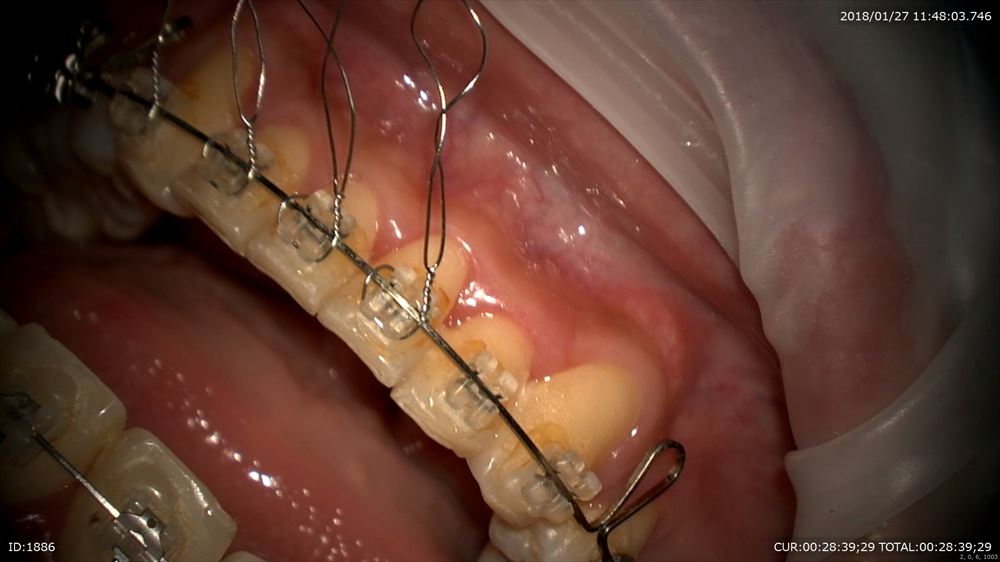

最後は矯正。4番の抜歯スペースのリトラクションの最終段階とトルクコントロール同時

マイクロで観察。トーイン。テイップバック

これでOK。春には外します!口元も綺麗になりました。